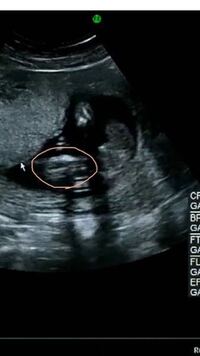

女の子 胎児- 妊娠中に性別が分かる前から現れる特徴〜男の子編〜 性別が分かる妊娠5ヶ月くらいから「お腹の子は男の子女の子どっちなんだろう・・・」って気になりますよね? 我が子は妊娠5〜6ヶ月の時にエコー診断で 男の子 と言われました。 しかしエコー診断 そして、胎児が成長してくると、 陰茎の根本に陰嚢が2つ確認できる ようになります。 女の子は陰茎のような目立つ外性器がないので判定が難しいのですが、 太ももの間に木の葉やコーヒー豆のような大陰唇が見え ます。

胎児のエコーでの性別 24週の妊婦健診で 子宮が見えたので女の子と言 Yahoo 知恵袋

女の子だろうとのことなのですが 女の子エコーの特徴の割れ目 コーヒー豆 がよく Yahoo 知恵袋

赤ちゃんの性別このエコーは女の子でしょうか 割れ目が見えるよう Yahoo 知恵袋